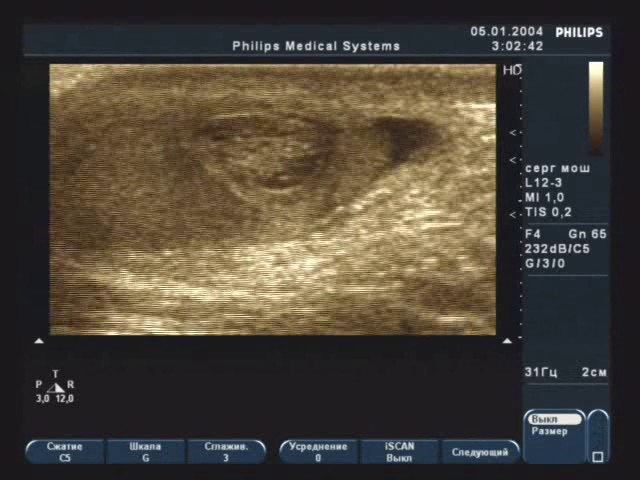

Для подтверждения диагноза применяются диафаноскопия и эхография. Диафаноскопия включает в себя освещение мошонки специальным фонарем, что позволяет определить местоположение новообразования. Эхография служит подготовительным этапом перед операцией, помогая установить точное место для разреза. Лабораторные исследования в случае перекрута гидатиды не имеют практического значения.